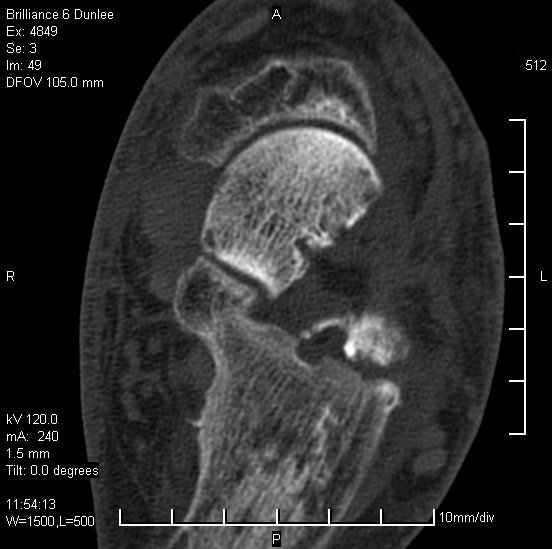

На лечении находится пациент 35 лет. Травма в сентябре 2008 г.- открытый вывих таранной кости

В день травмы ПХО, вправление вывиха, трансартикулярная фиксация. Рана зажила первично. С января нагрузка на конечность. С конца апреля- болевой синдром. На рентгенограммах и КТ признаки ас. некроза таранной кости, артроз подтаранного и голеностопного суставов.

1. Целесообразность формирования подтаранного артродеза (реваскуляризация таранной кости) с <разгрузкой> таранно-большеберцового сустава в условиях АВФ.

2. Первичное эндопротезирование голеностопного сустава. Сроки, тип эндопротеза.

У больного тотальный ас. некрох блока таранной кости, заинтересованы голеностопный и подтараный суставы. Эндопротезирование маловероятно на некротизированную кость. Изолированный подтаранный артродез таран не спасет.При артродезе всю некротизированную кость придется убрать.А далее замещение либо за счет большеберцовой кости, или удлинение на регенерате.